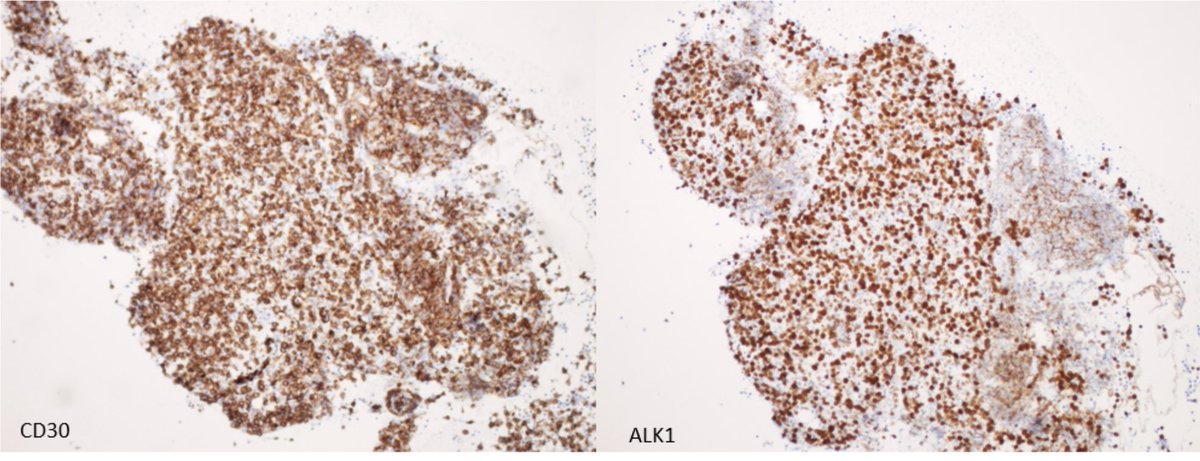

Pre-auricular nodule x 1month from 31yo patient, no other complaint. #pathtwitter #surgpath #ENTpath #hemepath #pathboards Einstein Montefiore Pathology Ridin Balakrishnan, MD Hansini Laharwani Siba El Hussein, MD Mitul B. Modi, MD Tristan Rutland MBBS FRCPA IFCAP Jerad Gardner, MD Kamran Mirza MD PhD - کامران مرزا

63/male with abdominal lymphadenopathy. DQ gave the initial clue to hemepath diagnosis. Positive CD3/5/7/25. CD30 diffuse, ALK1/CD20 negative. CD30+ Mature T-cell lymphoma. D/D ALCL or ATLL HTLV1 is positive! #cyto #hemepath #PathTwitter Kevin Kuan Yanhua Wang #bridgingcytoheme